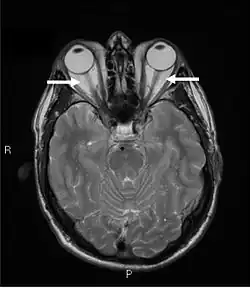

La oftalmopatía de Graves se diagnostica clínicamente por los signos y síntomas oculares que presenta, pero las pruebas positivas de anticuerpos (antitiroglobulina, antimicrosómica y antireceptor de tirotropina) y las anomalías en el nivel de hormonas tiroideas (T3, T4 y TSH) ayudan a respaldar el diagnóstico.La fotografía orbital es una herramienta interesante para el diagnóstico de la oftalmopatía de Graves y son útiles para controlar la progresión de la enfermedad en los pacientes. Sin embargo, no se justifica cuando el diagnóstico puede establecerse clínicamente. La ecografía puede detectar una orbitopatía de Graves temprana en pacientes sin hallazgos orbitales clínicos. Sin embargo, es menos fiable que el TAC y la resonancia magnética (RM) para evaluar la afectación del músculo extraocular en el vértice orbitario, que puede provocar ceguera. Por lo tanto, la TC o la RM son necesarias cuando se sospecha de una afectación del nervio óptico. En la neuroimagen, los hallazgos más característicos son el engrosamiento de los músculos extraoculares con preservación de los tendones, generalmente bilateral, y la proptosis.